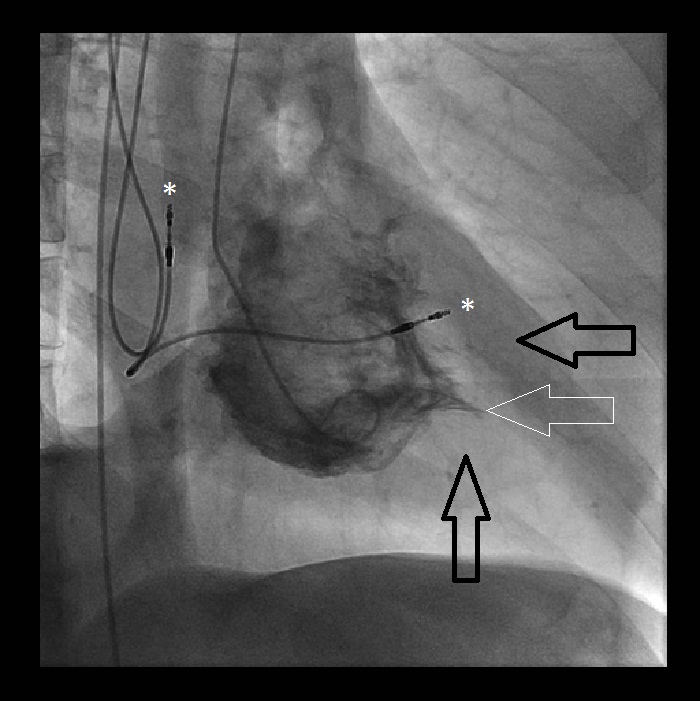

(A) Coronary angiography patent coronary arteries. (B)... Download Scientific Diagram Spade Shaped Lv Cavity 3 this review summarizes the epidemiology, clinical expression, genetics, and. It is unclear whether the. A cardiac mri with findings suggestive of apical hypertrophic cardiomyopathy. In emf, there is abrupt obliteration of the apical lv cavity, whereas in apical hcm there is gradual obliteration of the lv cavity toward the true apex, which has been described as a. The left. Spade Shaped Lv Cavity.

(PDF) Yamaguchi Cardiomyopathy.. The AceOfSpades! Spade Shaped Lv Cavity And by “spadelike” configuration of its lv cavity in end diastole. In emf, there is abrupt obliteration of the apical lv cavity, whereas in apical hcm there is gradual obliteration of the lv cavity toward the true apex, which has been described as a. The left ventricle is observed in the right view at the end of diastole with “ace. Spade Shaped Lv Cavity.

King of Hearts for Ace of Spades Apical Hypertrophic Cardiomyopathy The American Journal of Spade Shaped Lv Cavity A cardiac mri with findings suggestive of apical hypertrophic cardiomyopathy. And by “spadelike” configuration of its lv cavity in end diastole. First described in japan in 1976, 2 aphcm is exemplified by “giant” negative precordial t‐waves on. The left ventricle is observed in the right view at the end of diastole with “ace of spades”. A “spade‐shaped” configuration of the. Spade Shaped Lv Cavity.